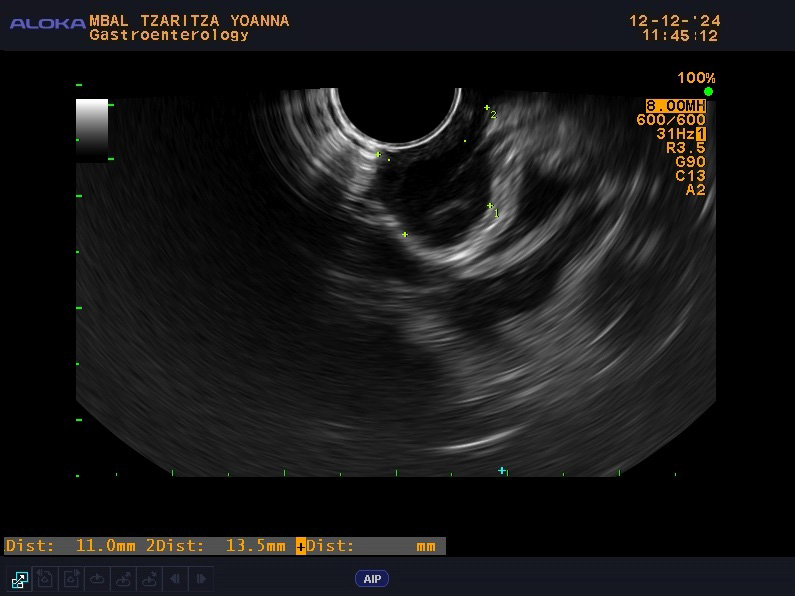

Throughout her hospital stay in our clinic, the patient exhibited normal laboratory results and no symptoms, without any other concomitant diseases or significant family history. From the physical examination (PE) the patient was slightly overweight with a body mass index (BMI)—29 without other pathological findings. The patient was scheduled for an EUS examination, which is the preferred modality for evaluating subepithelial lesions of the upper GI tract. During the EUS examination, an anechoic subepithelial lesion of the stomach was noted just below the oesophagogastric junction, corroborating the findings from the OGD. The lesion was 13.5 mm in size and displayed a typical “gut signature sign”, which is highly suggestive of a duplication cyst (Fig. 1). Given that other subepithelial lesions can appear intensely hypoechoic as lymphoma, leiomyomas, gastrointestinal stromal tumors (GIST), etc. and can mimic anechoic lesions, a CE-EUS was performed revealing enhancement confined to the wall of the lesion (Fig. 2) and confirming the diagnosis of a duplication cyst.

Fig. 1.

EUS examination with anechoic subepithelial lesion 13.5 mm in size at OGD and typical “gut signature sign”. Endoscopic ultrasound with the linear probe with anechoic subepithelial lesion 13.5 mm in size originating from the submucosal layer of the wall with “gut signature sign” highly suspicious for duplication cyst (the arrow). EUS, endoscopic ultrasound; OGD, oesophagogastroduodenoscopy.